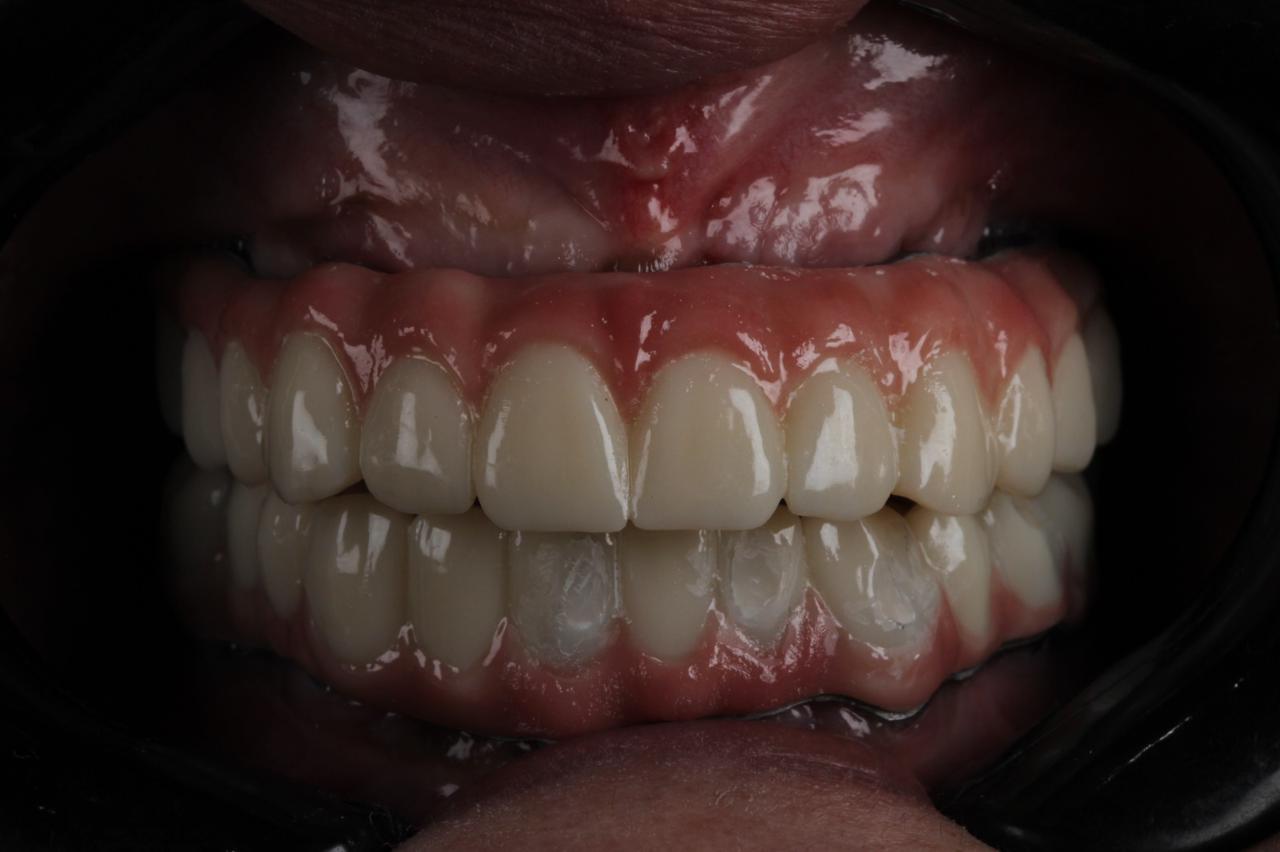

زراعه الأسنان